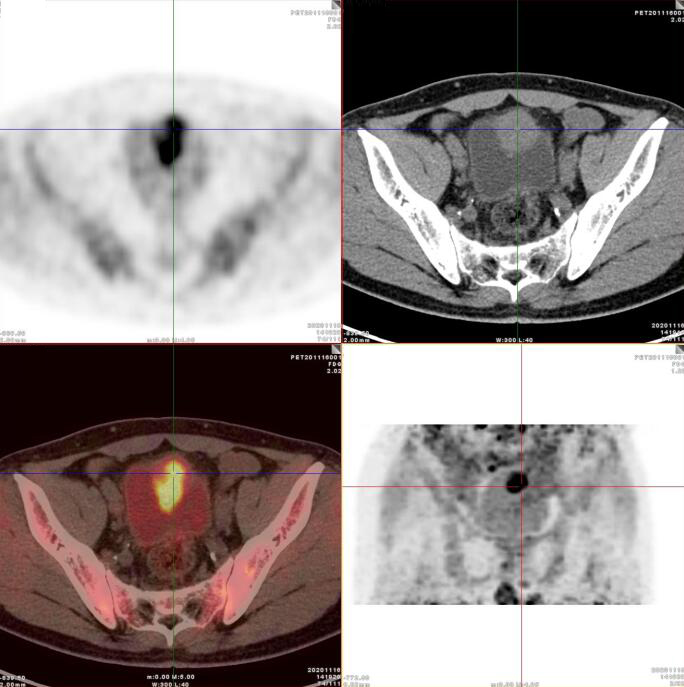

PET/CT影像圖

臍尿管擴(kuò)張,其管壁不均勻增厚,相應(yīng)區(qū)域膀胱頂前壁見一軟組織密度塊影,呈縱向生長(zhǎng),形態(tài)不規(guī)則,大小約3.3x3.8x6.3cm,內(nèi)見斑點(diǎn)鈣化!

膀胱頂前壁軟組織腫塊,放射性攝取SUV Max4.5

膀胱頂前壁軟組織腫塊,放射性攝取SUV Max4.5,延時(shí)4小時(shí)SUV Max8.3

臍尿管區(qū)及膀胱頂前壁軟組織腫塊,代謝增高,考慮臍尿管惡性腫瘤(臍尿管癌),建議穿刺活檢。